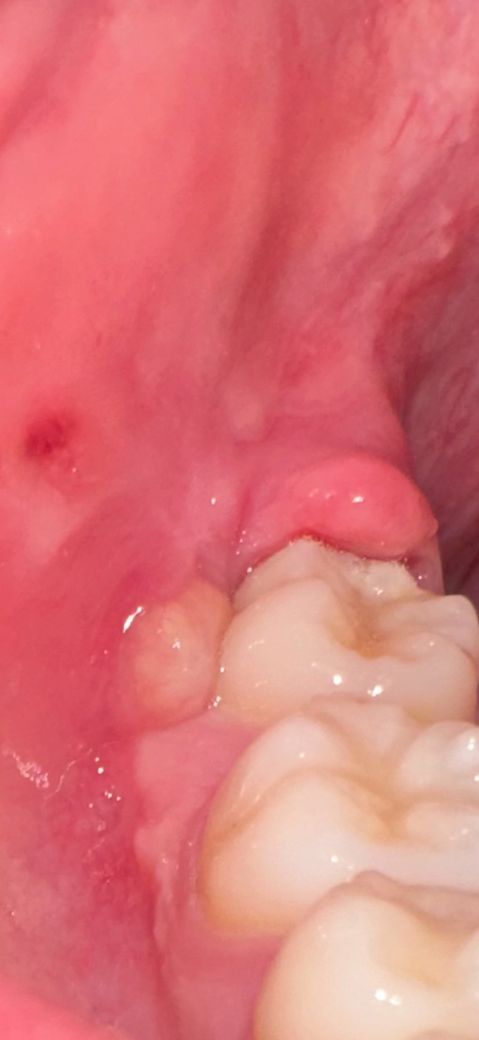

두 달전에 오른쪽 아래 사랑니 뽑았는데요.

화요일부터 사진처럼 염증이 너무 심해가지고

진통제 먹고 버텼는데 오늘은 오한에 열이 너무 심합니다. 염증하나로 이럴 수가 있나요? 귀도 아프고 목도 아프고 턱도 아프고 열나니까 제정신이아닌거갓타요

• 1번 째 사진